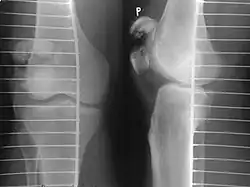

It typically results from a hard blow to the front of the knee or falling on the knee.[1]The patella can also be fractured indirectly. For example, a sudden contraction of the quadriceps muscle in the knee can pull apart the patella.[1]Diagnosis is based on symptoms and confirmed with X-rays.[3] In children an MRI may be required.[3]

Diagnosis is based on symptoms and confirmed with X-rays.[3] In children an MRI may be required.[3]